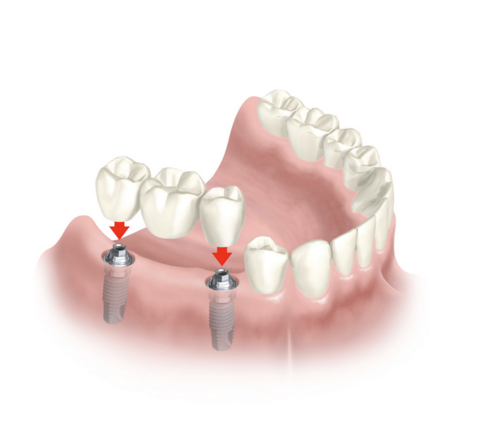

Puentes sobre implantes: Cuando faltan varios dientes, se pueden colocar puentes soportados por implantes. Por ejemplo, es posible reemplazar tres dientes con solo dos implantes.